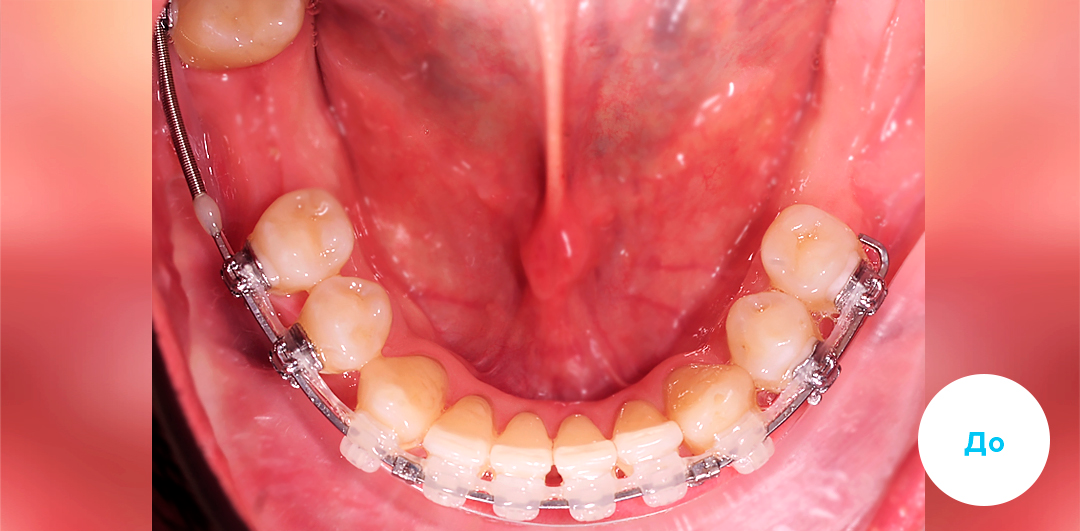

Результаты лечения